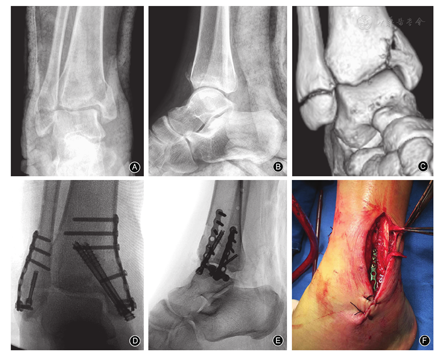

女,39岁,因摔伤致右侧踝关节肿痛、活动受限7 h至我院急诊就诊。查体:神志清,精神可,急性面容,生命体征平稳,右侧踝关节外侧、前方、内侧肿胀明显,右侧腓骨远端、内踝压痛明显。外院X线示右内、外踝骨折(图1A,图1B)。急诊以右踝关节骨折收住入院。

入院后予冰敷、抬高患肢、活血消肿、止痛等对症治疗,同时进一步行CT及三维重建检查,结果显示右外踝骨折、内踝粉碎性骨折(图1C)。根据Lauge-Hansen踝关节骨折分型为旋后内收型,AO/OTA分型为44-A2型。

伤后第8天,患者右踝关节肿胀消退、皮肤出现皮纹皱褶后行手术治疗。手术操作:①腰麻后患者取仰卧位,右臀部垫高,右大腿根部上气囊止血带,常规消毒铺巾。②取右腓骨外侧直切口暴露外踝骨折端,见外踝骨折端在下胫腓联合以远,近踝穴水平,远端骨折块较小,骨折端可见较多碎骨块;清理骨折端嵌入的软组织及碎骨块后复位骨折;复位后腓骨远端解剖型锁定钢板固定;固定后使用"C"型臂X线机透视,结果发现骨折端复位不满意,腓骨远端骨块固定不牢固,遂改用1块F3钢板(威高公司,中国)及1枚空心拉力螺钉(Wright公司,美国)固定。③取内踝弧形切口,暴露内踝骨折端;术中见内踝骨折线自下斜行向上延伸,远端骨折块较大,局部关节面压缩;清理骨折端,骨刀撬起压缩的关节面,复位骨折后,予2枚空心拉力螺钉及1块F3钢板内固定。术中透视示骨折复位满意,关节面平整(图1D,图1E)。④500 ml生理盐水冲洗伤口后,当缝合外侧切口时发现腓骨肌腱鞘局部有淤血,遂行探查;结果发现腓骨肌上支持带、腓骨短肌腱断裂,断端未回缩,腓骨长肌腱完整(图1F);清理两侧断端后,使用5-0 prolene缝线(强生公司,美国)"8"字缝合腓骨短肌腱,使用2-0可吸收缝线(强生公司,美国)依次修复腓骨肌腱鞘、腓骨肌上支持带。⑤逐层关闭切口,无菌敷料包扎后,踝关节中立位予石膏固定。